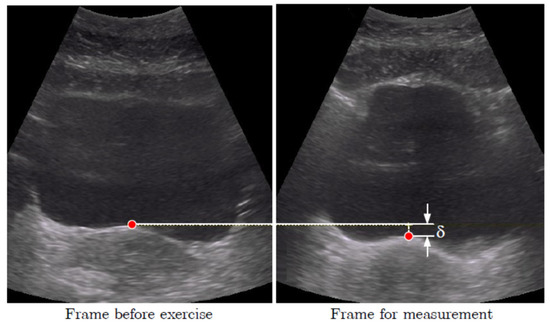

2.3. Data Processing